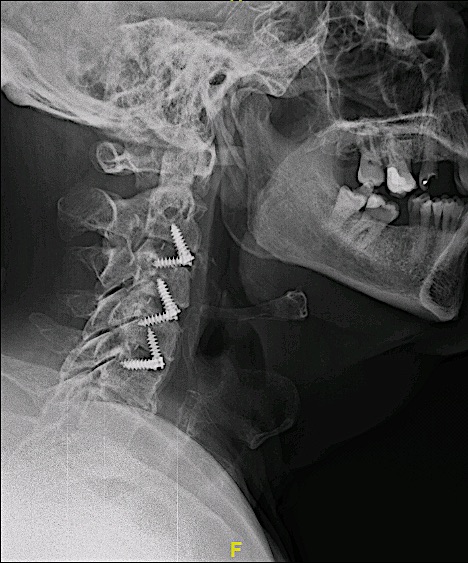

Paciente con clínica de mielopatía que presenta esta RM cervical con una estenosis de canal en segmentos tan inusuales.

El paciente fue intervenido vía anterior, con monitorización neurofisiológica intraoperatoria, sin incidencias.